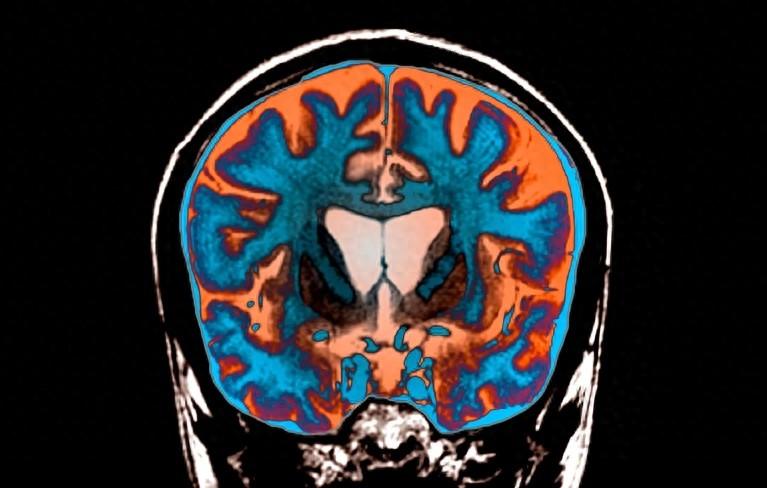

更令人心碎的是,這病不但折磨患者的身體,還會逐漸侵蝕他們的大腦。他們的性格可能變得特別暴躁,記性越來越差,腦子也越來越不好使。原來會彈鋼琴的,可能連簡單的曲子都彈不了了;以前是工程師的,可能連簡單的加減法都算不清楚了。最後,腦細胞會慢慢死掉,連說話和自己喫飯穿衣都成問題。

150次就是最關鍵的閾,一旦達到,那就徹底完蛋了!細胞裏一堆基因都開始失控,就像公司財務系統崩潰了一樣,賬目全亂了。沒幾個月,腦細胞就開始死亡。這過程根本剎不住車,後面CAG重複次數會蹭蹭往上漲,直到300、500,甚至800次,患者病情也會不斷加重直至死亡。

最絕的是,科學家發現就算病人已經開始出現症狀,他90%的腦細胞其實還是健康的!這就意味着,要是能想辦法阻止CAG的瘋狂複製,沒準還真能治好這病,哈佛和麻省理工現在正在爲此努力。